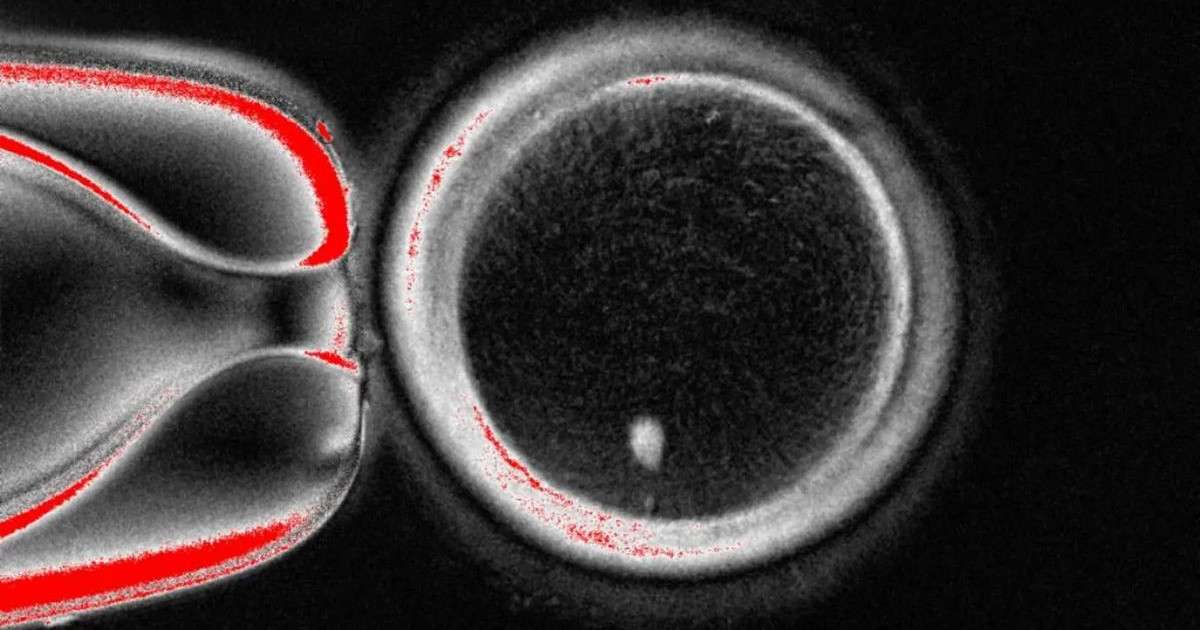

Το αποτέλεσμα ήταν η παραγωγή 82 ωαρίων, τα οποία γονιμοποιήθηκαν στο εργαστήριο. Παρότι η πλειονότητα των εμβρύων παρουσίασε χρωμοσωμικές ανωμαλίες και δεν προχώρησε πέρα από την τρίτη ημέρα, περίπου το 9% έφτασε στο στάδιο της βλαστοκύστης – το σημείο όπου συνήθως μεταφέρονται τα έμβρυα σε ασθενείς που υποβάλλονται σε εξωσωματική γονιμοποίηση. Οι επιστήμονες διέκοψαν τότε την καλλιέργεια, θέτοντας σαφές όριο στη μελέτη τους.

Η διαδικασία, που οι ίδιοι ονόμασαν μιτομείωση, παρουσίασε αρκετά ζητήματα. Το κύριο πρόβλημα είναι ότι τα κύτταρα δέρματος φέρουν ήδη 46 χρωμοσώματα, ενώ τα φυσιολογικά ωάρια και σπερματοζωάρια έχουν μόλις 23. Έτσι, όταν ένα τέτοιο τροποποιημένο ωάριο γονιμοποιείται, το έμβρυο καταλήγει με ένα επιπλέον σετ χρωμοσωμάτων, κάτι που το καθιστά μη βιώσιμο. Για να ξεπεράσουν το εμπόδιο, οι ερευνητές χρησιμοποίησαν ηλεκτρικό παλμό και μια ουσία που ονομάζεται roscovitine, ώστε να μιμηθούν τη φυσική διαδικασία της μείωσης των χρωμοσωμάτων. Παρ’ όλα αυτά, οι περισσότερες δομές εξακολουθούσαν να έχουν σοβαρά λάθη στον αριθμό ή στον συνδυασμό των χρωμοσωμάτων.